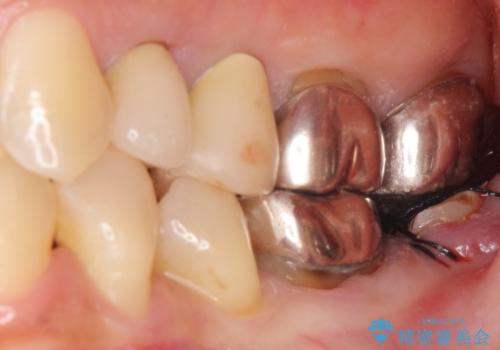

ご希望により、隣の親知らず(左下8)を移植しました。

移植後、生着を待って根管治療及び補綴修復を行いました。

親知らずの移植により、自分の歯を用いて咬合機能を回復することができ、大変喜んで頂けました。